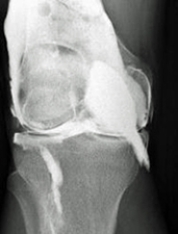

Which of the following imaging techniques illustrated in the pictures would be the most efficient to discover if there is a loose body within a joint?

Q15: Which of the following imaging techniques illustrated

Q17: Which of the following imaging techniques illustrated